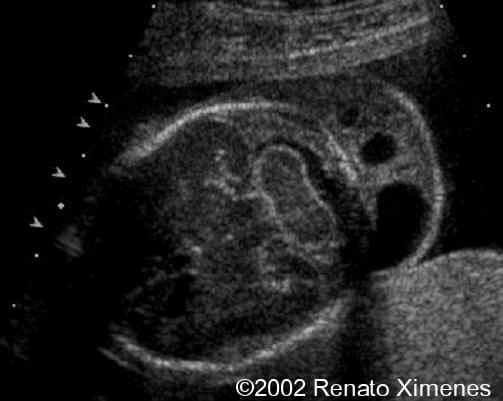

The cystic hygroma extends down the back of the fetus and pleural effusions are visible:

case0072-3

case0072-4

case0072-5